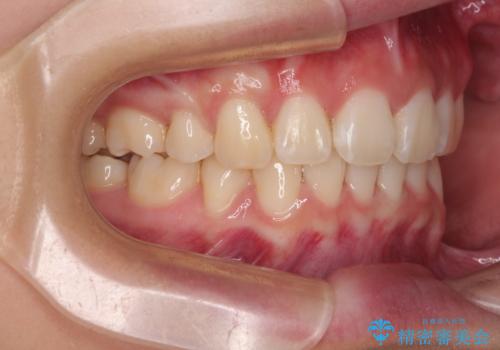

- 前歯部のデコボコと口元が出ているのが気になるとのことで来院された患者様です。

口元の突出感の解消と、このままデコボコを解消するとさらに出っ歯傾向になってしまうことを考慮し、上下左右の小臼歯を抜歯しクリアブラケットにて矯正していくこととしました。

舌突出癖を改善するトレーニングを一生懸命やっていただいたおかげで2年以内に治療を終えることができました。